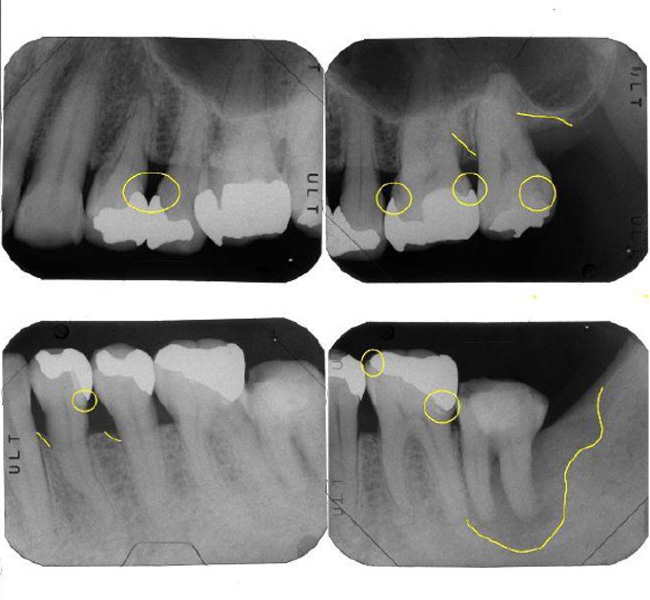

治療前

治療後

| 治療内容 | 全顎治療:歯周病治療、抜歯、根管治療、 咬合治療・矯正治療、フルメタルクラウン(保険) |